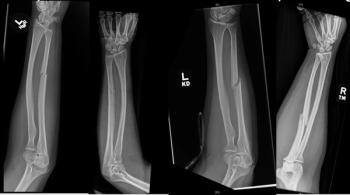

Radiologists have the opportunity to identify women suffering intimate partner violence by detecting a specific type of forearm fracture.